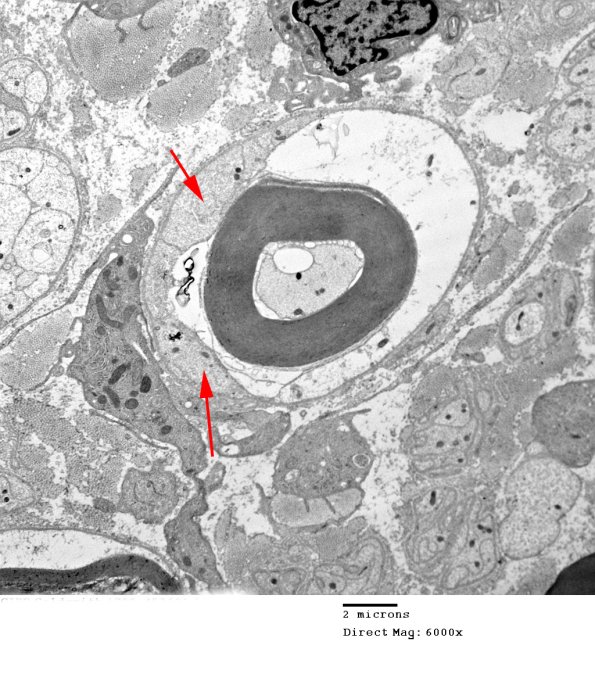

Although the majority of this large Schwann cell is pale, other Schwann cell processes (arrows) are not. (electron micrograph)